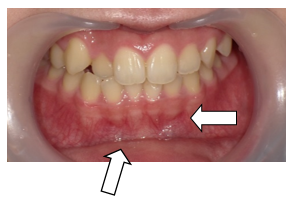

① 上下顎右側 側切歯の反対咬合

② 上顎右側 犬歯 八重歯

下の歯並びは気にならないが、下の顎が前に出てきた感じがし、本人が気になり始めた。以前、西村歯科で反対咬合をムーンシールドで治した。(6か月~1年間だと思う。)